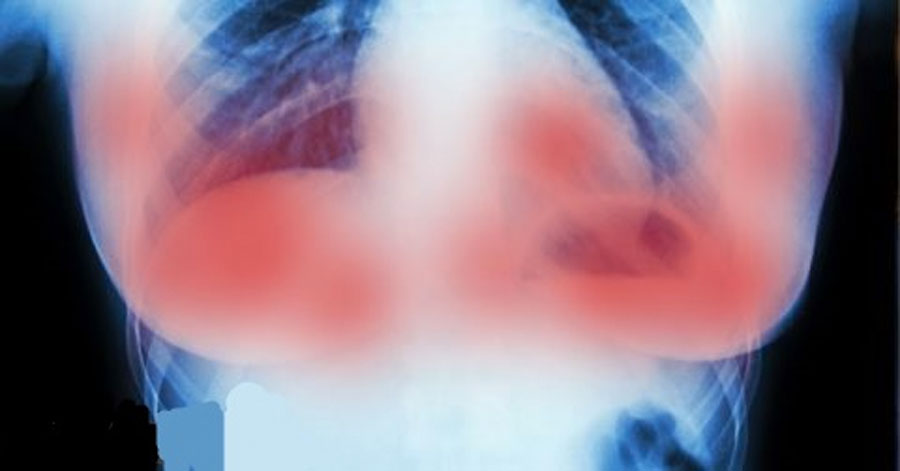

Cualquier día en que un nuevo estudio muestra una cura potencial para el cáncer es un buen día. En esta ocasión científicos en Europa podrían haber hecho un gran avance en la lucha contra el cáncer de mama.

El cáncer de mama es el más común entre las mujeres, alrededor de 1 de cada 8 mujeres estadounidenses lo desarrollará en su vida; el ensayo clínico puede haber encontrado una manera de deshacerse de él de una vez por todas en el futuro.